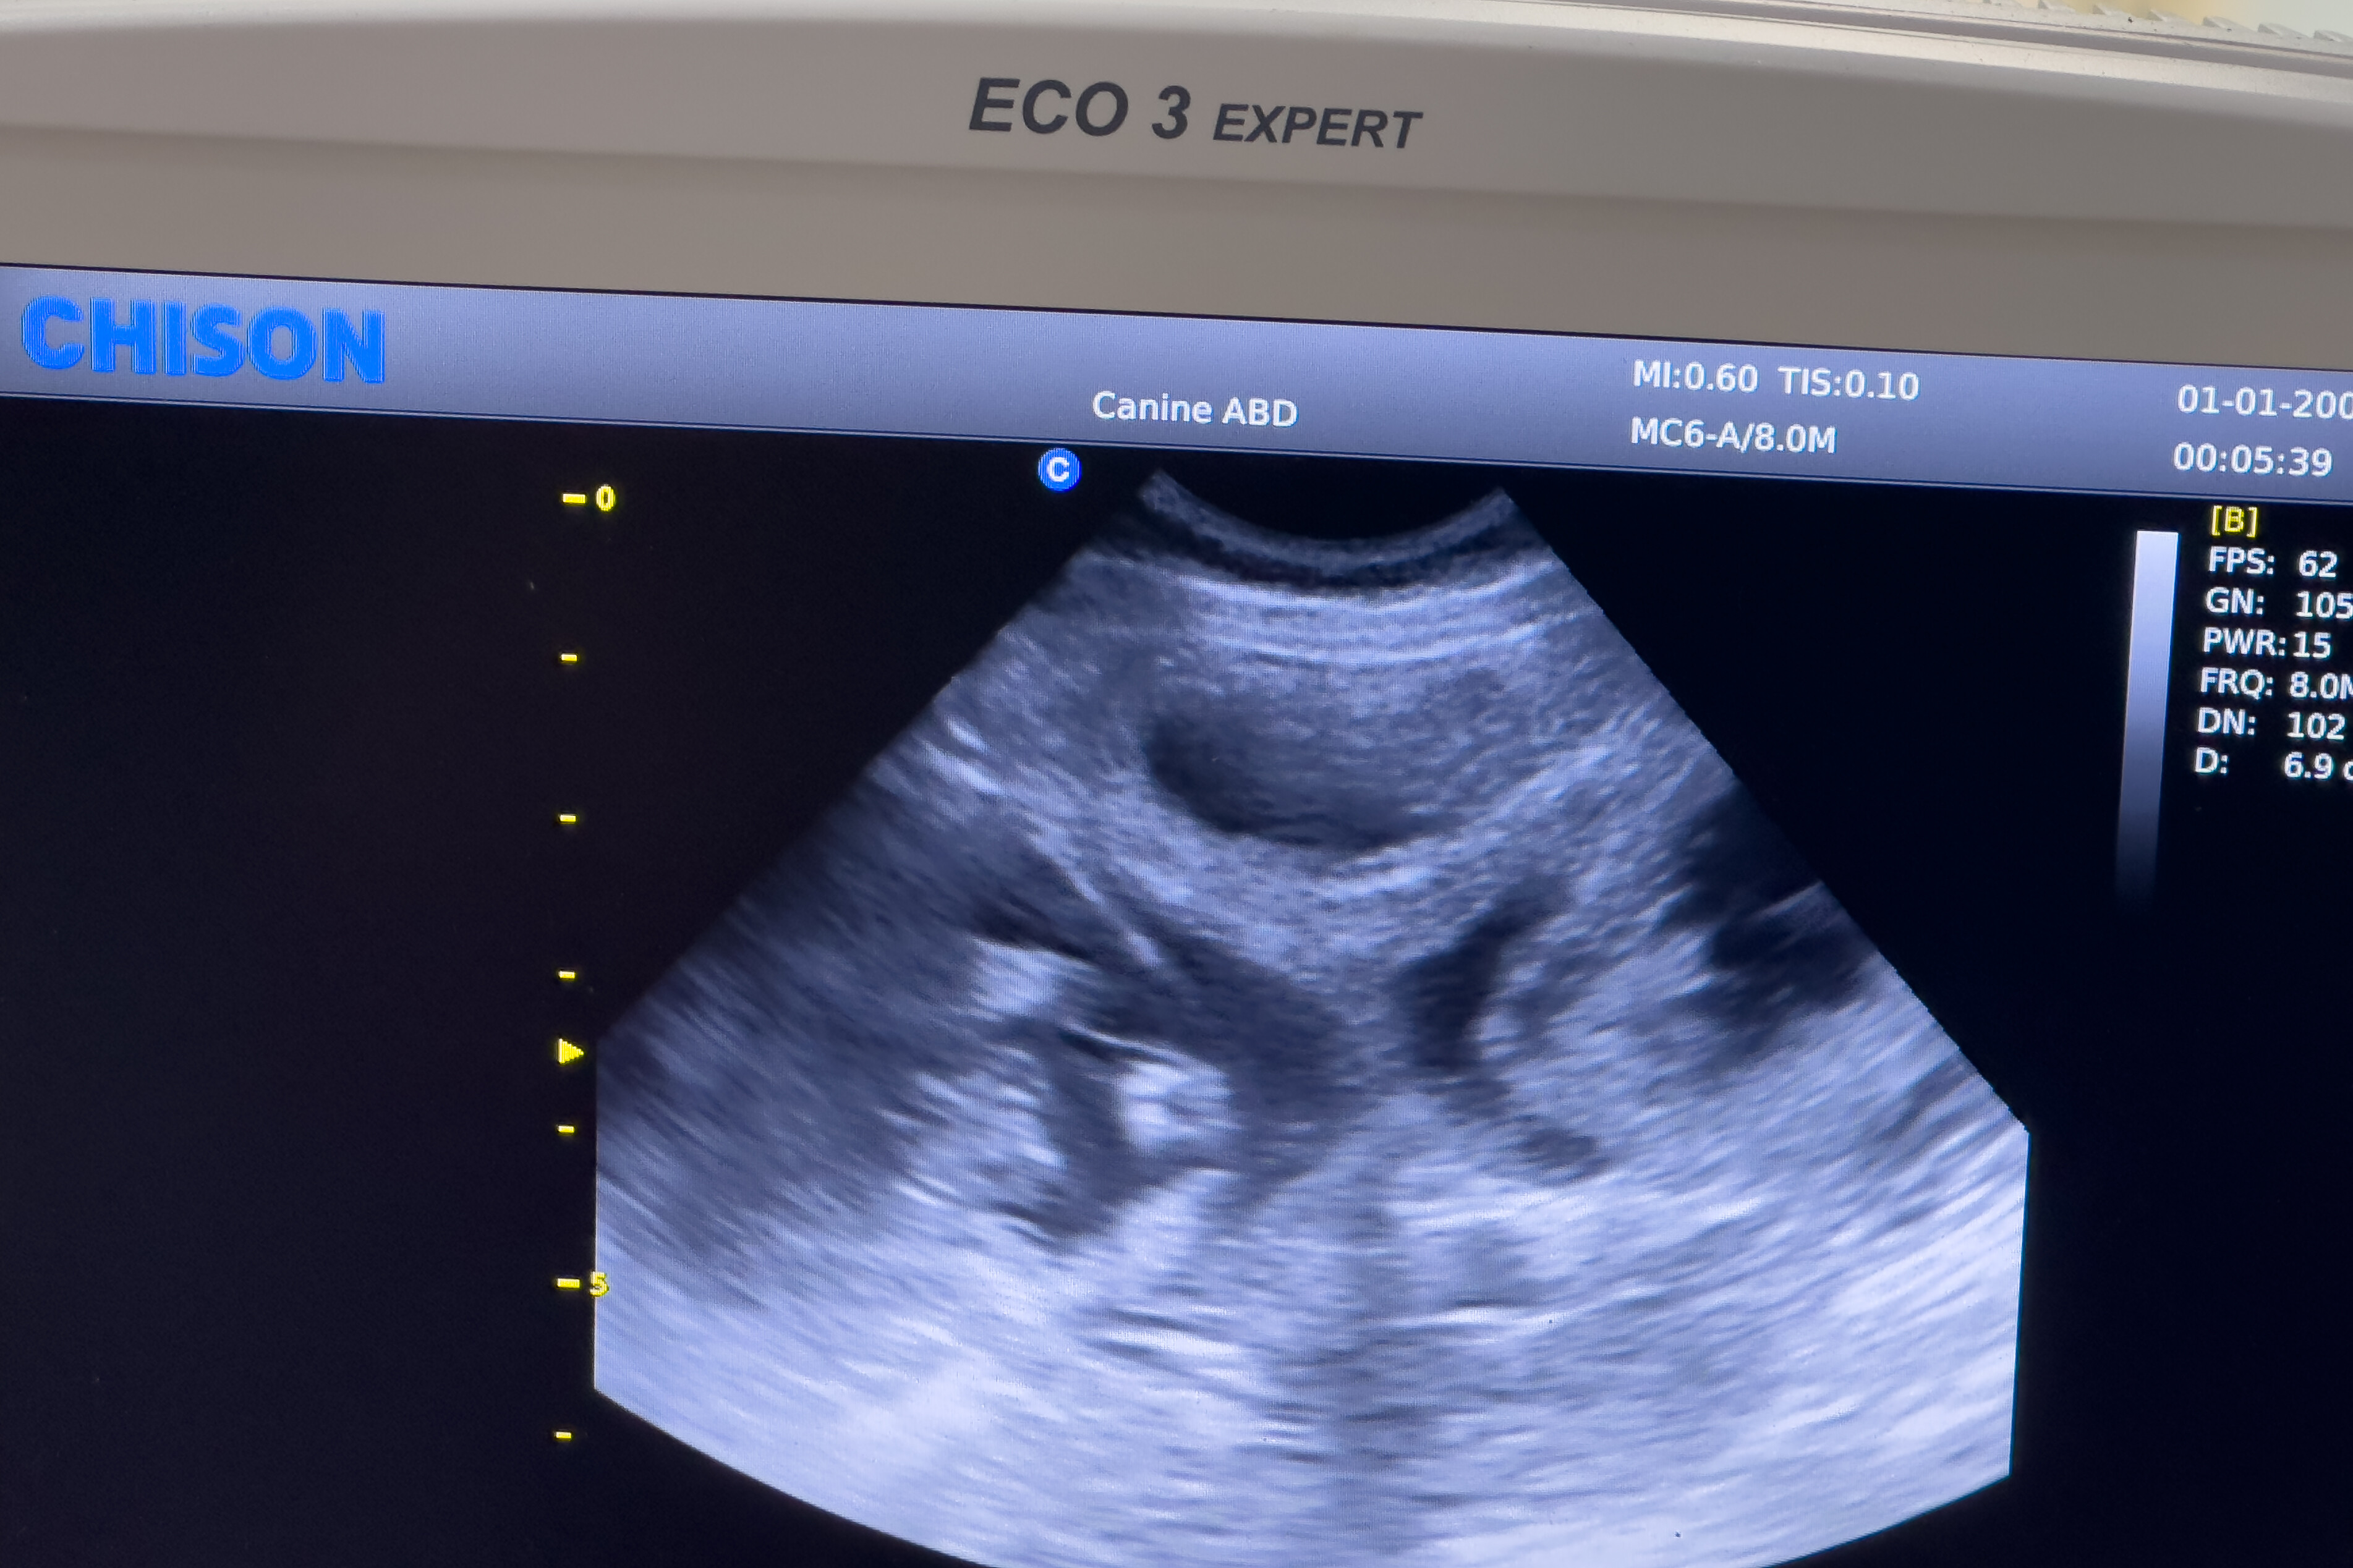

Еще за пару недель до этих фотографий мы сходили к ветеринару сделать US и посмотреть что же носит в себе наша корги. Результат нас ошарашил… Вот вы сколько щенков видите? И я ни одного….